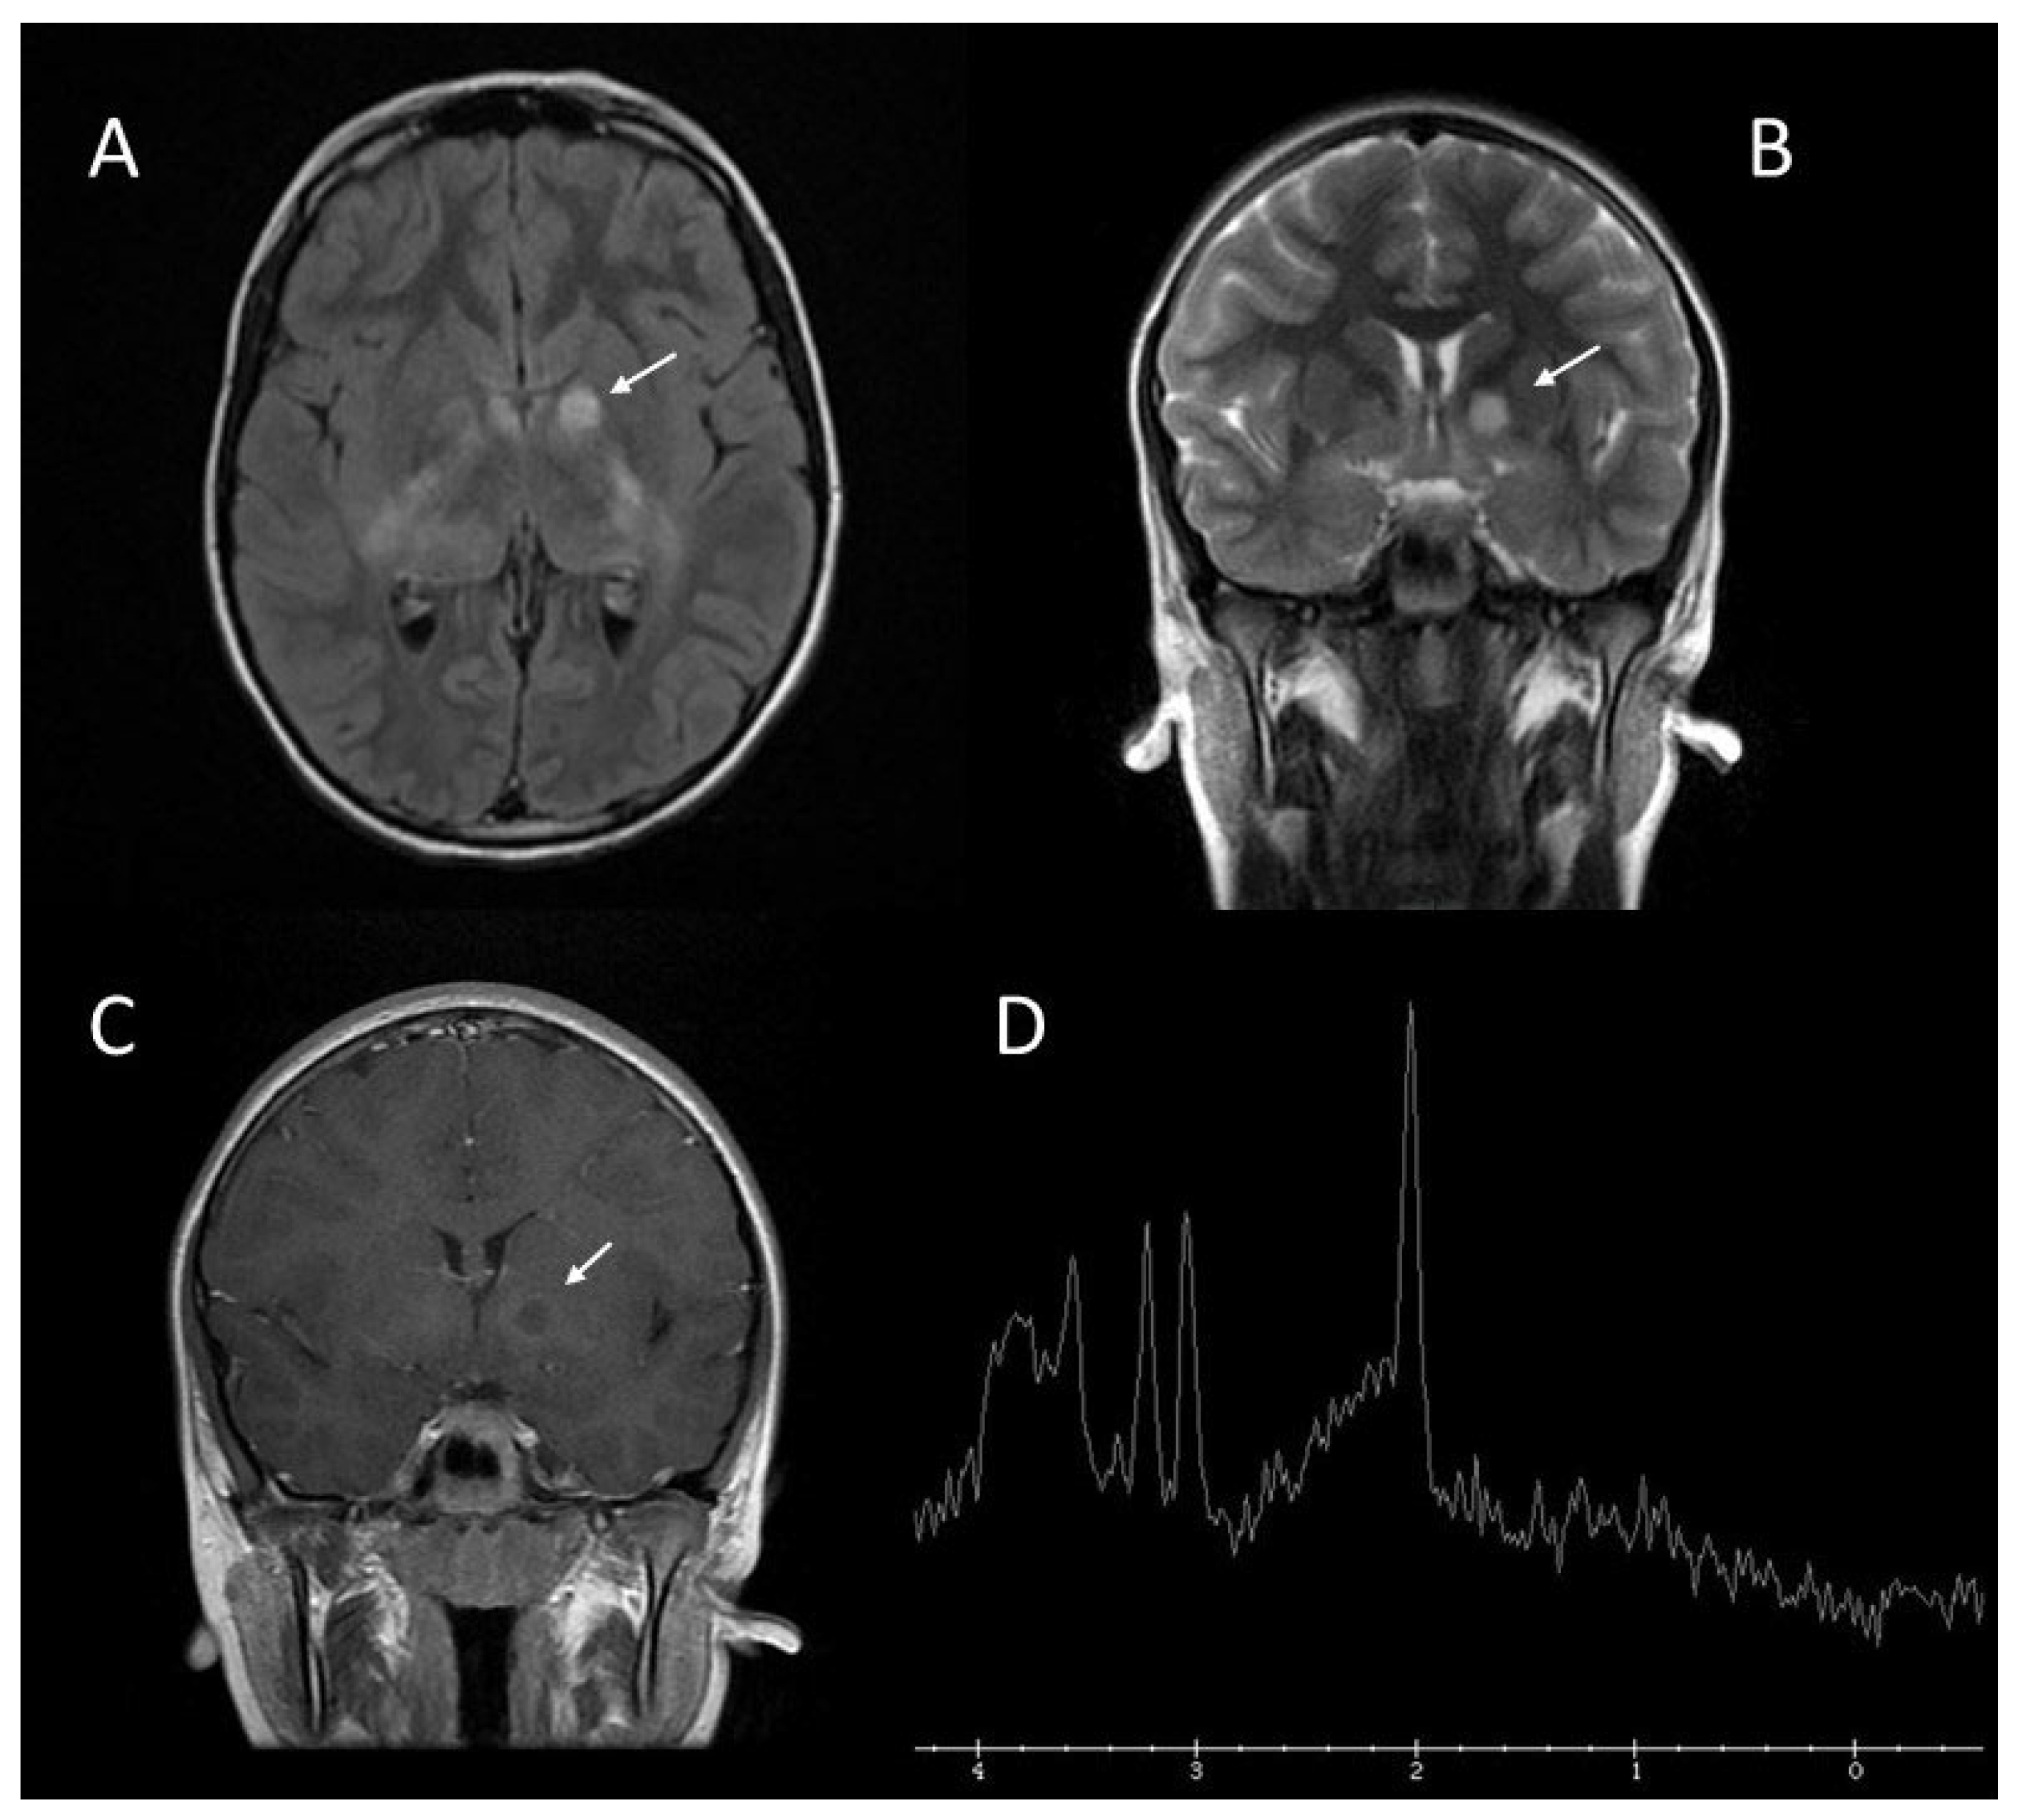

2.3. Brain Abnormalities: UBOs or FASI

| Brain abnormalities: UBOs or FASI | 43–93% | Areas of increased signal intensity on T2-weighted MRI sequence, not visualized on T1-weighted images and do not show mass effect or contrast enhancement; |

| Rarely seen in patients older than 20 years; | ||

| The cerebellum, the brainstem, and the basal ganglia are the regions most involved. | ||